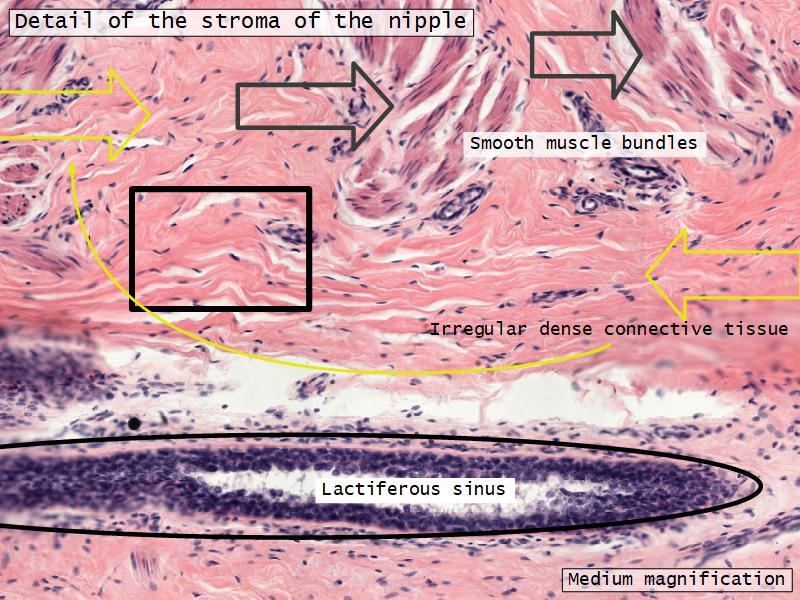

What are the main morphological features of the nipple?

(4)

Morphology

- Covered with skin

- Consists of dense collagenous connective tissue

- Interlaced with smooth muscle fibres

- Contains openings of lactiferous ducts

Stroma

- Collagenous connective tissue

- Irregular dense connective tissue

- Smooth muscle

- Fibres and bundles

- Lactiferous sinusses

- Stratified cuboidal epithelium